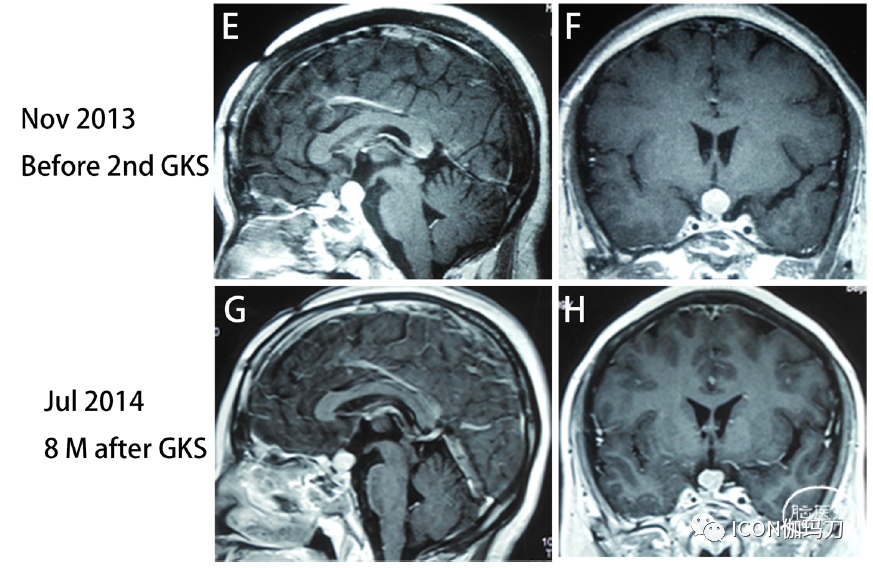

因为肿瘤继续生长或复发,2012年11月,她接受第一次伽玛刀放射外科治疗(GKS)治疗(图2A和B)。七个月星期治疗后,MRI显示肿瘤大小略下降(图2 C和D)和血清泌乳素水平降低了从200.0 ng / mL(样本不稀释)57 ng / mL。然而,2013年11月MRI显示肿瘤大小明显增大(图2E和F),血清泌乳素水平再次上升至289.0 ng/mL(补充图1),她接受了第二次GKS治疗。8个月后第二个星期的治疗,MRI在2014年7月表示,肿瘤大小略有缩小(图2 G和H)和血清泌乳素水平下降到126.0 ng / mL(补充图1)。尽管接受过两次GKS的治疗,再次在2014年10月她的症状视野缺损和右眼视力缺损。MRI显示肿瘤迅速扩大,鞍上延伸并包覆右侧ICA(图3A和B),血清泌乳素再次增加到339.0 ng/mL(补充图1)。视力减退症状明显改善,血清泌乳素水平降至108.0 ng/mL(补充图1)。肿瘤切除后病理检查显示有丝分裂活性增加,Ki-67指数上升至10%(图4B和C)。2014年11月推荐使用卡麦角林;然而,在卡麦角林治疗1个月后,肿瘤继续扩大,激素继续增加(补充图1)。然后,我们推荐替莫唑胺(TMZ)治疗,但她拒绝这种化疗,因为TMZ的费用过于昂贵,医疗保险无法覆盖垂体瘤患者使用该药的费用。

她经历了左眼视力丧失,MRI报告肿瘤体积显著增加,并压迫视交叉(图3E和F),血清泌乳素水平升至200.0 ng/ mL(未稀释样本)(补充图1)。行第四次经颅垂体瘤次全切除术(图3G和H);然而,视力下降没有改善,术后出现中枢系统感染。经抗生素治疗及腰椎引流后,中枢系统感染治愈。垂体肿瘤切除后的病理结果显示Ki-67指数增加到20%(图4F)。2016年3月,她面对痛苦和软弱的右腿,和MRI显示硬膜内的类似质量的第四腰椎(图3 I和J)。全身ECT等报道,多个高代谢(hypermetabolic)焦点被发现在第五腰椎(补充图2),血清泌乳素水平再次升至200.0 ng/mL(标本未稀释)(补充图1)。经后路硬膜外病变完全切除(图3K和L)。术后右腿疼痛和无力明显恢复。但血清泌乳素水平没有显著下降(补充图1)。切除的椎管内肿瘤的组织学检查显示,免疫组化(IHC)PRL为强阳性,而其他垂体激素为阴性。Ki-67指数上升到30%(图4H和I)。病理结果与分泌泌乳素垂体癌(PCs)的转移一致。随访期间,血清泌乳素水平持续升高,2016年10月最后一次血清泌乳素检测结果为356.0 ng/mL(补充图1)。不幸的是,鞍区肿瘤继续快速进展,患者于2017年10月死亡。

图3.(A)和(B)在第三次经额开颅前,2014年10月MRI显示肿瘤迅速扩大,鞍上延伸并包绕右侧ICA。(C)和(D)第三次开颅后,将肿瘤近全切除。(E)和(F)第四次经额开颅前,2015年1月MRI报告肿瘤体积明显增加,并压迫视交叉。(G)、(H)第四次开颅后,肿瘤次全切除。(I)和(J)腰椎MRI显示第四腰椎水平硬膜内髓外肿块。(K)和(L)术后MRI提示硬膜内髓外病变完全切除。